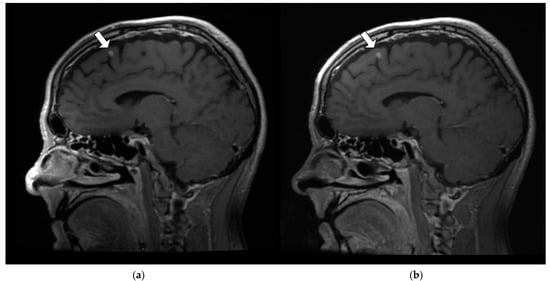

3.3.5. Image Uniformity and Depiction of Fine Anatomic Detail